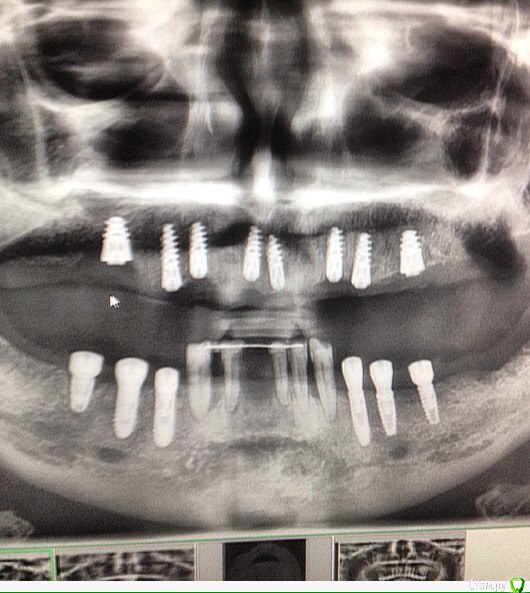

Doctor1981 Опубликовано 30 июля, 2017 Поделиться Опубликовано 30 июля, 2017 Здравствуйте, уважаемые коллеги! Помогите определить, что за имплантаты на нижней челюсти. На верхней стоят ROOTFORM . История банальная , имплантаты ставила шарашкина контора , которая благополучно закрылась. Контакты с врачом и клиникой потеряны. Заранее спасибо! Ссылка на комментарий

red_butler Опубликовано 30 июля, 2017 Поделиться Опубликовано 30 июля, 2017 Вы думаете по снимку такого качества можно что то понять? Сделайте обычную ОПГ. И покажите фото ФДМов 1 Ссылка на комментарий

bullbull Опубликовано 2 августа, 2017 Поделиться Опубликовано 2 августа, 2017 34, 35 на корею похожи Ссылка на комментарий

red_butler Опубликовано 25 августа, 2017 Поделиться Опубликовано 25 августа, 2017 на груви похожи, а нет плоского снимка? Ссылка на комментарий

Kovalov Igor Опубликовано 29 августа, 2017 Поделиться Опубликовано 29 августа, 2017 может быть BB dental implant? Ссылка на комментарий